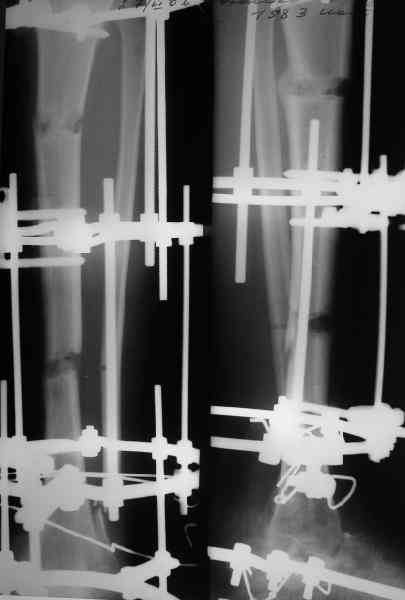

Аппарат был снят окончательно только после введения стержня, то есть оставалось по одной спице в проксимальном и дистальном метафизах большеберцовой кости, спицы в пятке. Фото во время рассверливания в приложении.

ВМ> 2. достаточно-ли одного проксимального статического винта,нет ли

ВМ> опасения проседания регенераратов и разрушения винта

Стержень 12 мм, винт диаметром 6 мм, костная трубка вокруг хорошая. Перелом такого винта пока не наблюдали ни разу на нескольких сотнях

пациентов.